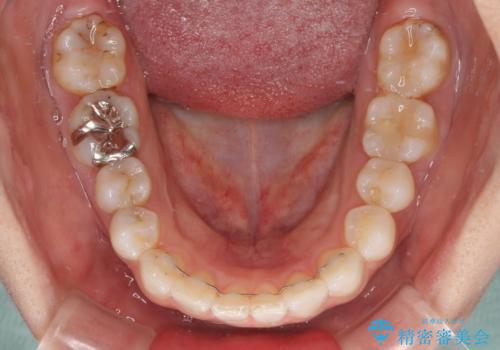

- 前歯のデコボコを治したいとのことで来院された患者様です。

上下顎ともに歯列全体の後方移動とIPR(歯と歯の間を削る)によってデコボコが解消するように設計し、インビザラインにより治療を行うこととしました。

しっかりと装着時間を守ってくださったのですが、途中妊娠にともなう悪阻や出産といったイベントがあり、予定よりも治療期間が長くなりました。